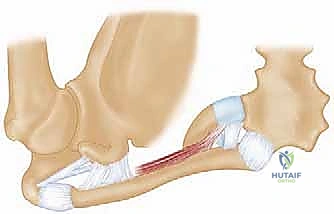

لا يمكن ببساطة خياطة الأربطة الممزقة لضمان الاستقرار. لذلك، يستخدم الدكتور هطيف تقنية متقدمة لإعادة البناء باستخدام "رقعة وترية" (Tendon Graft).

* أخذ الرقعة: غالباً ما تؤخذ من وتر العضلة الرشيقة (Gracilis) أو العضلة نصف الوترية (Semitendinosus) من ركبة المريض نفسه (Autograft)، أو استخدام رقعة صناعية طبية عالية الجودة.

* حفر الأنفاق العظمية: يتم حفر ثقوب دقيقة جداً في عظم الترقوة وعظم القص باستخدام أدوات جراحية متطورة.

5. تمرير الرقعة وتثبيتها (تقنية الرقم 8)

يتم تمرير الرقعة الوترية عبر الثقوب العظمية بنمط يشبه الرقم 8 (Figure-of-eight). هذه التقنية الميكانيكية الحيوية توفر قوة استقرار هائلة تحاكي قوة الأربطة الطبيعية (الرباط الكبسولي والرباط الضلعي الترقوي).